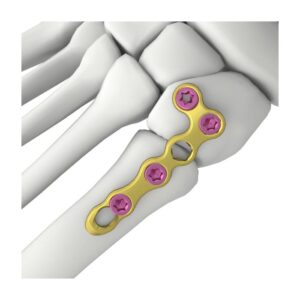

SET DE PLACAS PARA RADIO DISTAL

Conjunto de cuatro placas anatómicas de bloqueo para la fijación quirúrgica de fracturas del radio distal, con opciones volares, dorsales y extendidas para adaptación precisa y estabilidad óptima según el patrón de fractura.